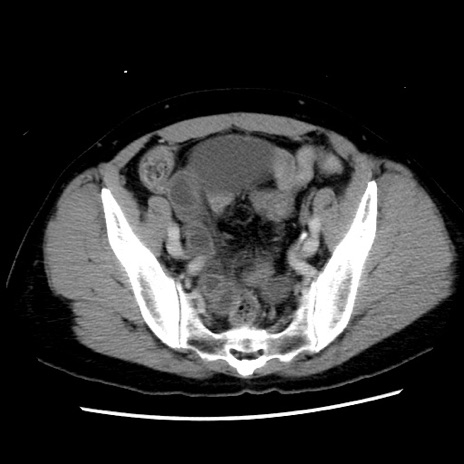

冠状断像

【症例】 50歳代女性

【主訴】 腹痛

【現病歴】前日生レバーを食べた。今朝に排便あり。 昼前に突然発症の腹痛を生じ、当院救急外来を受診した。

【既往歴】 子宮筋腫にてで子宮全摘後

【身体所見】 意識清明、腹部:平坦、軟、下腹部やや左を中心に圧痛・反跳痛あり、筋性防御あり

【データ】WBC 7800、CRP 0.07